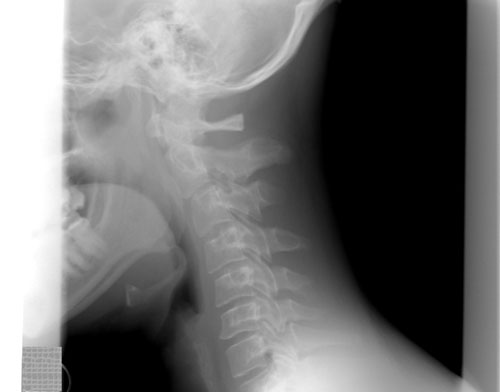

Cervical dystonia (CD) is an excruciating neurological condition involving the neck muscles. Most commonly, people with cervical dystonia experience their chin twisting toward 1 of the shoulders. Some may experience their ear tilting towards the shoulder, the chin tilting up, the chin tilting down, or a combination. As well, a jerking motion may also occur with the condition. Neck pain that radiates into the shoulders is also common for many, making the disorder disabling.

The symptoms of cervical dystonia include involuntary contractions of the muscles in the neck that lead to abnormal postures and movements. In some cases, these contractions might be continuous. In other cases, these contractions can occur as spasms that resemble tremors.